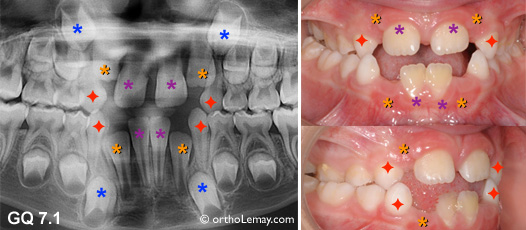

Extractions sélectives asymétriques chez un garçon de 9 ans visant à tenter d’améliorer l’asymétrie de la ligne médiane inférieure et la position des incisives. Voir légende ci-dessous.

Dans d’autres cas, comme celui illustré ci-dessus, il peut y avoir asymétrie dans la position des incisives sans qu’une canine ne soit tombée.

(A, B) Les incisives se sont déplacées vers la droite (flèche) de la ligne médiane (pointillé jaune) et une latérale inférieure (*orange) est bloquée et ne peut sortir par manque d’espace .

Il serait alors indiqué d’extraire la canine non du côté où il manque d’espace (droite du patient) mais du côté opposé (gauche) (* bleu = canines temporaires, losange rouge = canine à extraire). Extraire la canine droite ne ferait qu’augmenter la tendance qu’ont les incisives à migrer vers la droite en leur donnant plus d’espace.

Après un délai de ± 12 mois, l’autre canine (* bleu 2) pourra être extraite. Il est possible qu’après un tel délai la position des incisives se soit améliorée un peu sans aucune autre intervention.